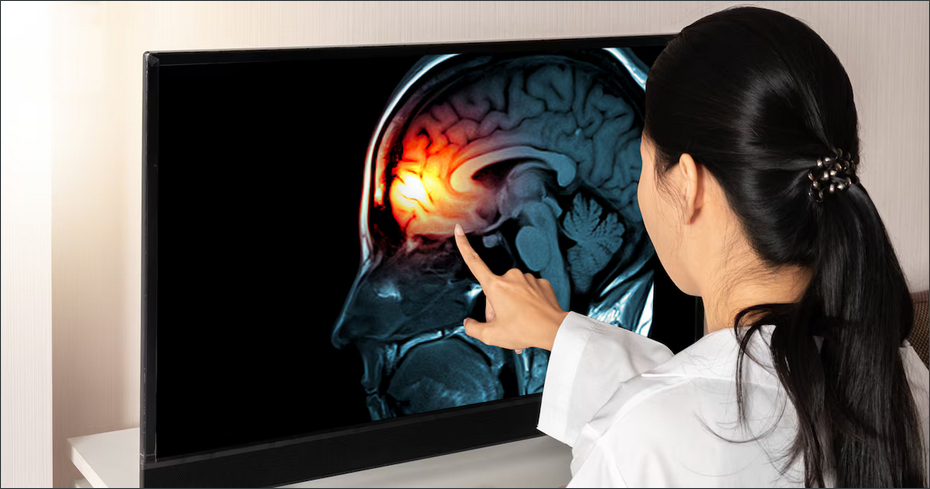

James Kimmel : Des études en neurosciences et des scanners cérébraux réalisés dans plus de soixante universités à travers le monde ont révélé que votre cerveau, en situation de vengeance, ressemble à un cerveau sous l’emprise de la drogue. Ce sont les mêmes circuits qui sont activés pour la dépendance à la drogue, l’alcool, le tabac ou le jeu. Lorsque vous ressentez un grief, le sentiment d’avoir été lésé, que ce soit réel ou imaginaire, c’est d’abord douloureux. Pour rééquilibrer cette sensation, votre cerveau active les circuits du plaisir, de la récompense et de l’envie liés à la dépendance. C’est une courte période qui vous donne une sensation d’euphorie temporaire créée par la montée de la dopamine, mais qui s’estompe rapidement. A ce moment-là, vous voulez revivre cette euphorie encore et encore. En fin de compte, vous voulez infliger de la douleur à une autre personne pour votre propre plaisir, parce que vous-même souffrez.

Dans l’addiction, la dernière pièce du puzzle est le cortex préfrontal. Il s’agit de votre circuit de maîtrise de soi et de fonction exécutive, qui est là pour vous empêcher d’adopter des comportements qui auraient des conséquences négatives sur vous ou sur d’autres personnes. Or, quand vous cherchez à vous venger, dans la majorité des cas, il y aura des conséquences négatives pour vous comme pour votre cible. Ce que nous constatons dans les scanners cérébraux, c’est que ce circuit de maîtrise de soi est désactivé chez un certain nombre de personnes. Il ne fonctionne donc pas correctement pour vous empêcher de vous livrer à des actions autodestructrices.